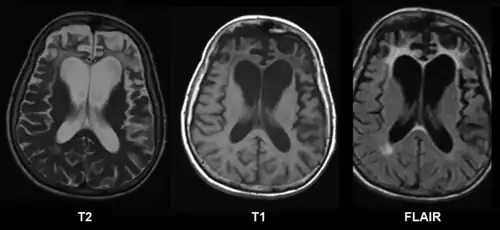

CT and MRI are most commonly used to observe the brain for cerebral atrophy. A CT scan takes cross sectional images of the brain using X-rays, while an MRI uses a magnetic field. With both measures, multiple images can be compared to see if there is a loss in brain volume over time.[20]